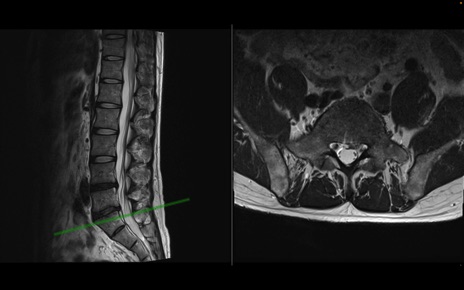

【整形】TIPS症例1 腰椎MRI 横断像と矢状断像

【症例】40歳代男性

【主訴】左臀部〜大腿後面痛み

【現病歴】2週間前から腰痛あり。2日前に夜中にくしゃみをした際に激痛が出現。疼痛強いため来院。

【身体所見】左臀部〜大腿後面、下腿後面のしびれ。SLR -/+ 30度、うつ伏せ困難、筋力低下なし。

異常所見と診断は?